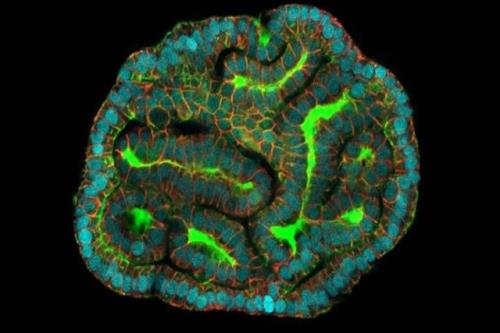

پرورش ریه، کلیه و روده مینیاتوری با مایع حاملگی